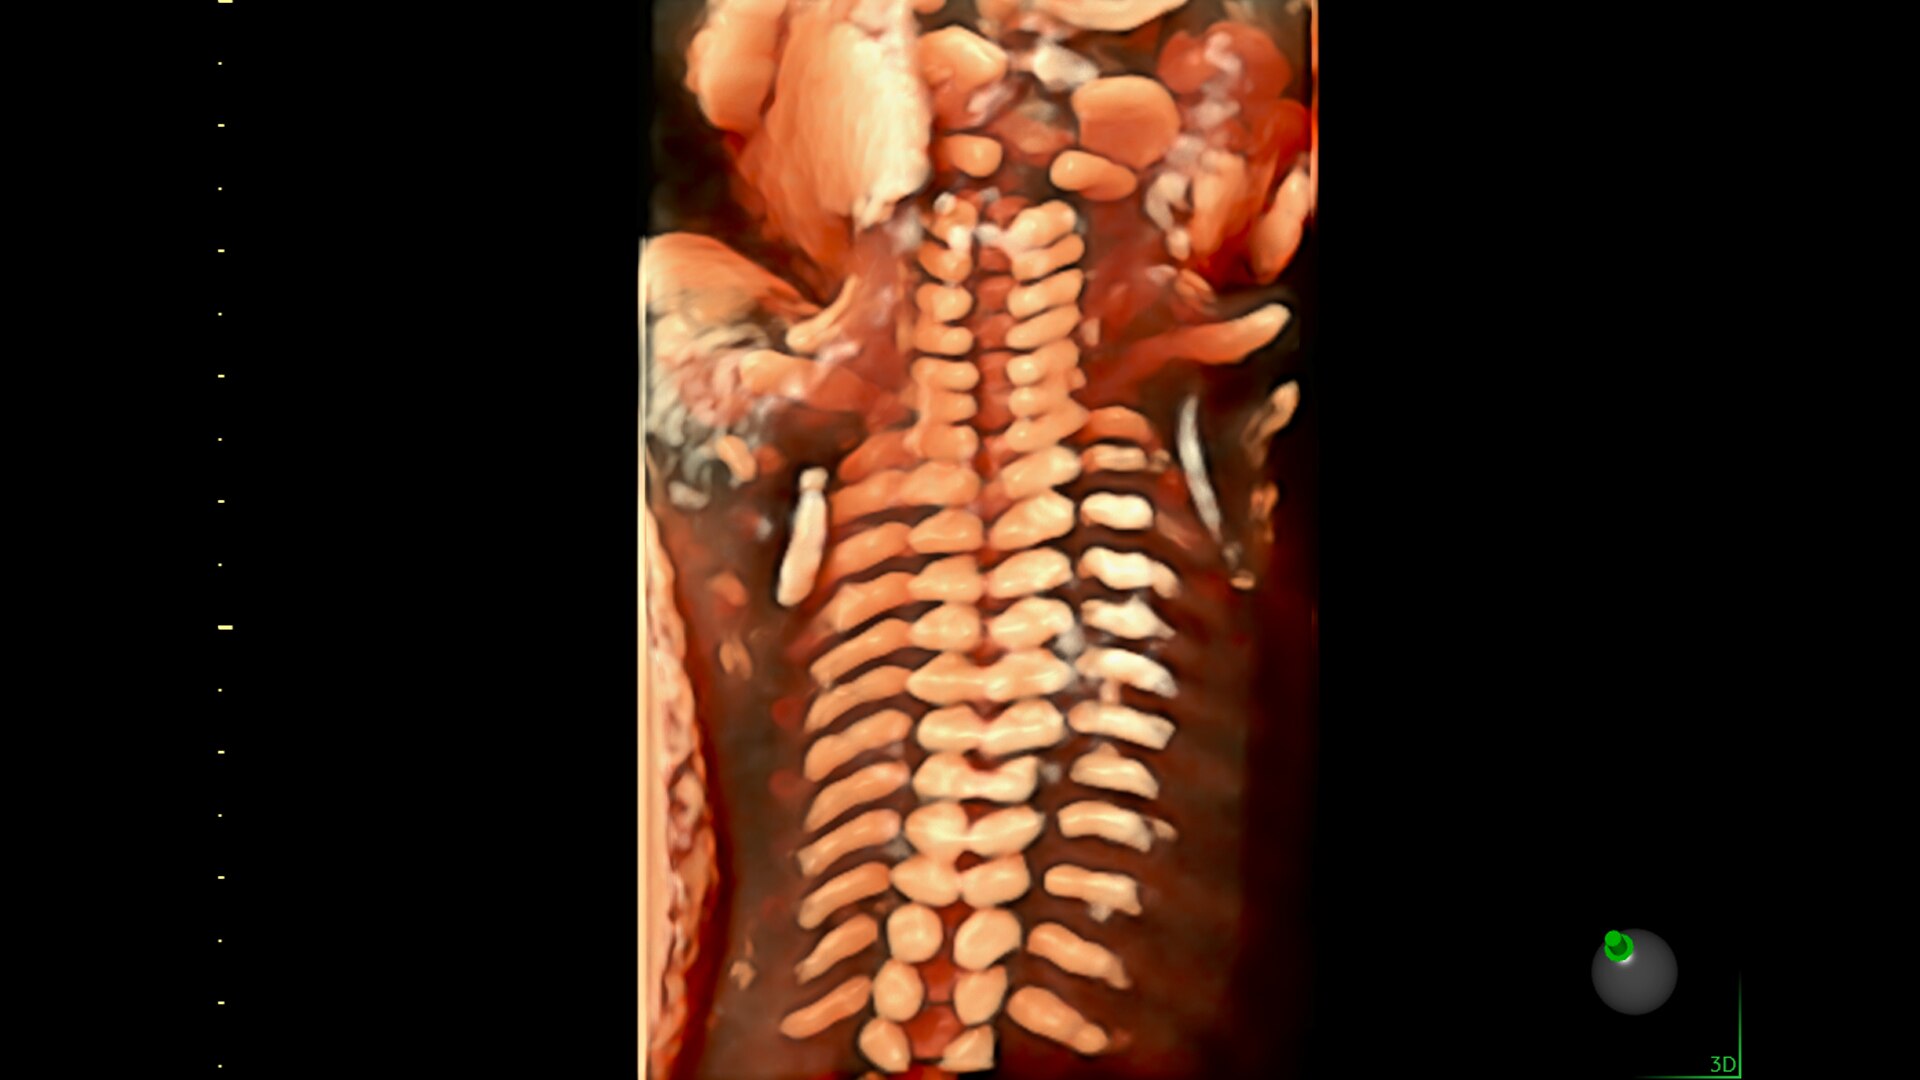

Advanced beamforming capabilities work in harmony with expert-level probes to deliver faster processing speeds and frame rates for enhanced detail and contrast resolution, greater color quality and sensitivity, and exceptional 3D/4D.

Spine Trace

Welcome to easy 3D in 1/2 the time. Simply trace the spine and the system automatically acquires the volume and displays the coronal view - with 83% less keystrokes.